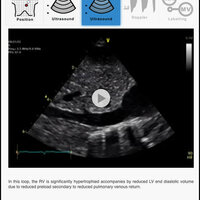

The purpose of this application is to support neonatologists who are actively involved in a recognized TnECHO training program. This application includes videos of probe position, 2D echo loops, color Doppler loops, and labelling of the various structures. This application is aimed at familiarizing neonatologists with basic echocardiography views and aiding self directed learning, but does not represent complete training. This application has not been designed to teach how to screen, diagnose or evaluate congenital heart disease, although it is recognized that neonatologists must be familiar with normal anatomy and deviations from this. Although structural heart disease should always be considered when performing a TnECHO evaluation, if the former is clinically suspected a paediatric cardiologist should always be involved. Image optimization techniques are not discussed as it is usually machine specific.